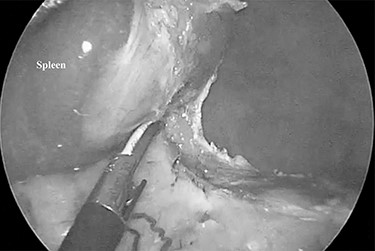

The patient was placed in the right lateral decubitus position. The standing positions of the surgeon and the assistant were on the right or left of the patient depending on the surgical site. Initially, a 12-mm port was introduced through the lateral margin of the left rectus abdominis muscle at the level of the umbilicus. After establishment of pneumoperitoneum with an intra-abdominal pressure of 10 mmHg, two 3-mm ports were inserted in the left upper quadrant at the subxiphoid and left subcostal margin along the mid-axillary line. The accessory spleen was carefully explored through the abdomen. The spleen was mobilized from the lower to upper direction. The initial dissection involved release of the lower pole of the spleen with dissection of the splenocolic ligament, and the spleen was freed from the splenorenal ligament toward the posterior aspect of the splenic hilus using laparoscopic coagulating shears under the guidance of a 3.3-mm needlescope (Karl Storz SE & Co. KG) (Fig. 2). Subsequently, short gastric vessels (Fig. 3) were divided, and the upper pole of the spleen was mobilized with the division of the splenophrenic ligament. Then, the splenic hilus was divided using a linear stapler (Fig. 4). The isolated spleen was then placed in an impermeable bag (Endo-Catch II; Covidien Co. Ltd.) and extracted via a 12-mm port after morcellation using the placenta forceps without extending the initial 12-mm incision (Fig. 5). After irrigation with normal saline and confirmation of hemostasis around the resected area without inserting a suction drain, only the 12-mm port site was only closed, and the 3-mm port sites were left open.